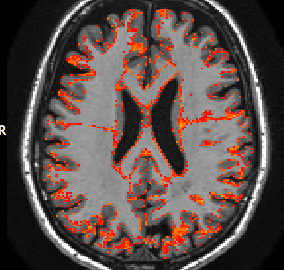

This section investigates the number of Monte Carlo samples and the segmentation performance of the proposed network. Fig. 8(a) suggests that using samples is enough to achieve good segmentation. Further increasing the number of samples has relatively small effects on the DCS. Fig. 8(b) plots the voxel-wise segmentation accuracy computed using only the voxels with an uncertainty less than a threshold. The voxel-wise accuracy is high when the threshold is small. This indicates that the uncertainty estimation reflects the confidence of the network. Fig. 9 shows an uncertainty map generated by the proposed network. The uncertainties near the boundaries of different structures are relatively higher than the other regions.

With this theoretical insight, we are able to estimate the uncertainty of the segmentation map at the voxel level. We extend the segmentation network with a convolutional layer before the last convolutional layer. The extended network is trained with a dropout ratio of 0.5 applied to the newly inserted layer. At test time, we sample the network N times using dropout. The final segmentation is obtained by majority voting. The percentage of samples which disagrees with the voting results is calculated at each voxel as the uncertainty estimates.